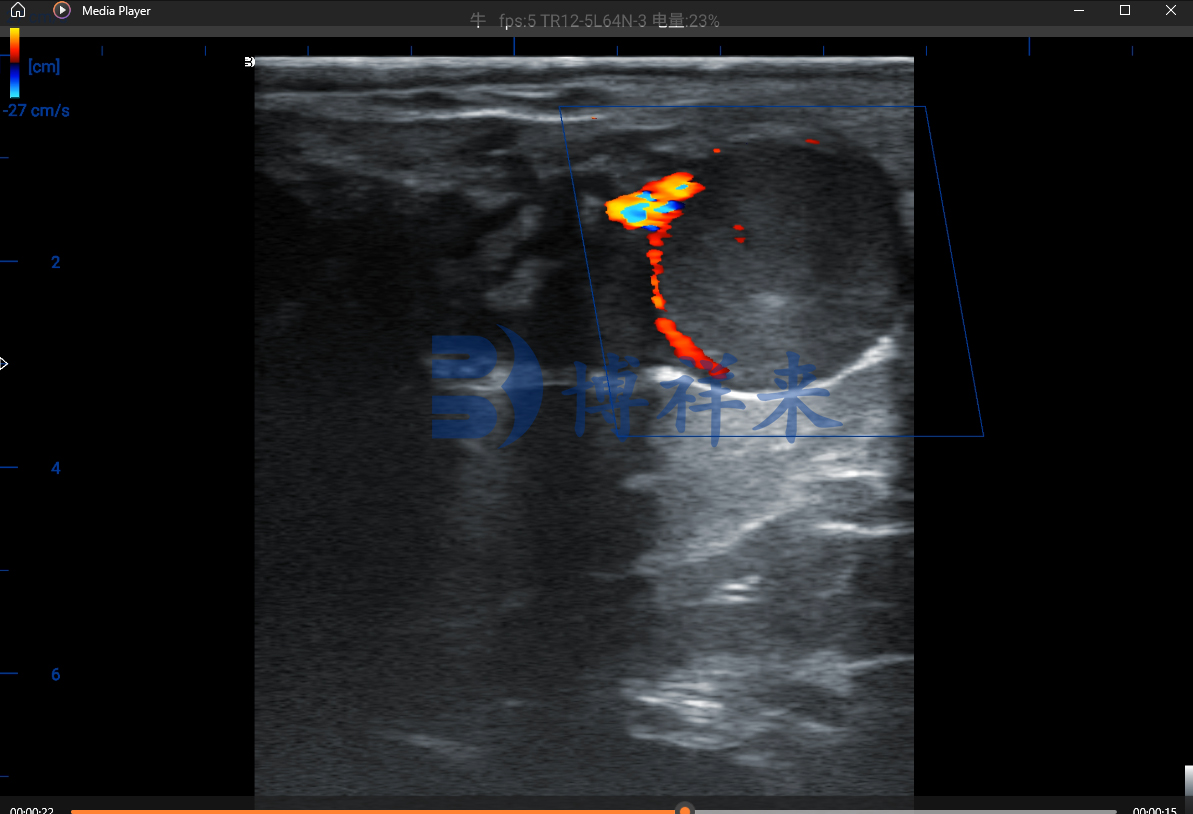

BXL-S300通过多普勒彩色成像模式,能够直观显示黄体周围的血流分布。

这种基于“血流动力学”的测孕方法,不仅比常规黑白B超更敏感,也能在母牛尚未出现肉眼妊娠迹象时提前做出判断。